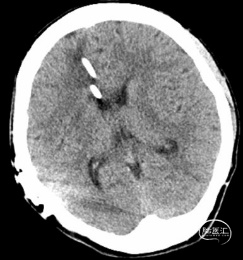

辅助检查:我院头颅CT(图1)提示:小脑肿瘤切除术后,左侧小脑半球软化灶。脑积水V-P分流术后,脑室系统轻度扩张。头颅MRI平扫+黑水成像+DWI(图2A)提示:脑积水V-P分流术后,交通性脑积水伴间质性脑水肿,脑室系统轻度扩张。头颅增强MRI提示:小脑肿瘤切除术后,左侧小脑半球软化灶,伴脑室穿通畸形;脑积水V-P分流术后,脑积水伴间质性脑水肿,幕上脑实质未见明显异常密度灶,静脉窦未见明显异常。颈椎MRI(图2B)示:未见明显异常。

图1. 头颅CT提示脑积水V-P分流术后,脑室系统轻度扩张。